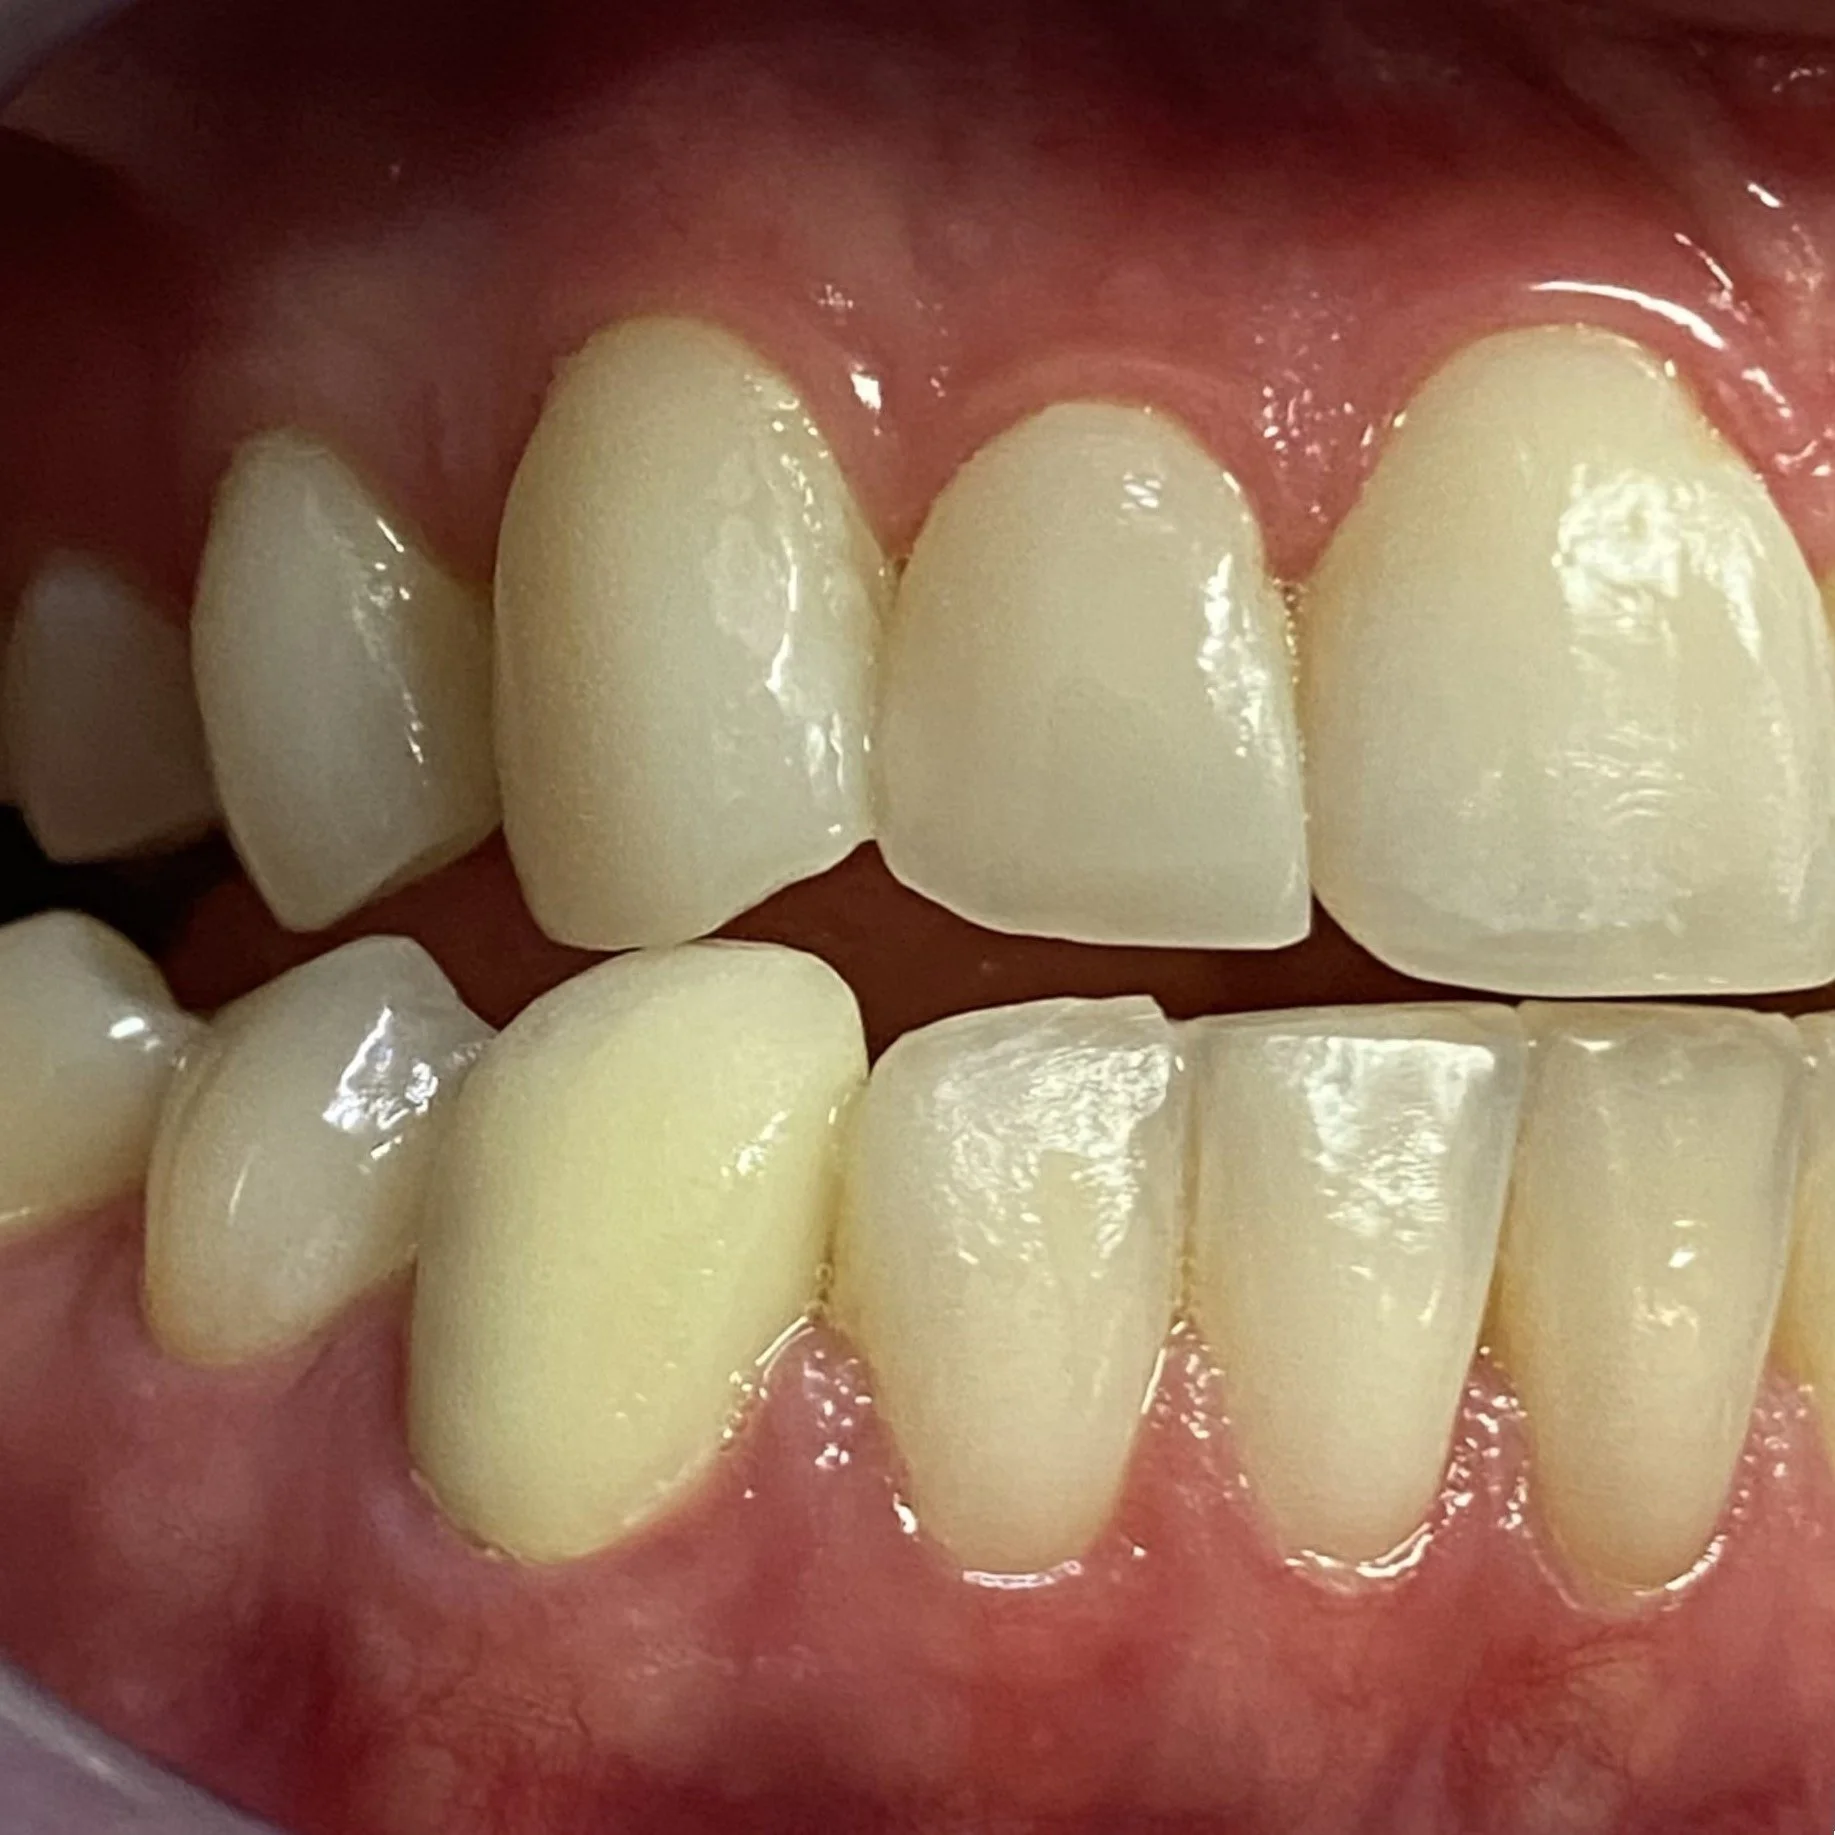

THE RIGHT VIEW ILLUSTRATES AN ALMOST UNPROTECTED RIGHT BITE

THE LEFT VIEW HIGHLIGHTS A COW-LIKE LEFT JAW MOVEMENT WHICH IS AN UNPROTECTED LEFT BITE AND THE WIDE UNESTHETIC SPACE IN THE TOP LEFT NUMBER 2 REGION

And an unprotected right bite associated with poorly positioned canine teeth and a recessed 12, 13 and 14 teeth.

Here we see how the lower 43 canine is not only short in stature but rotated in towards the tongue.

The right extreme jaw movement caused by over stretching of the left TMJ jaw joint as there was no restriction present with non-engaging right canine teeth. This movement repeated over multiple times both during the day and night significantly contributed to facial asymmetry.